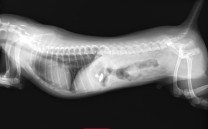

椎間板ヘルニアグレード4に対して片側椎弓切除術を行った1例

橈骨、尺骨骨折に対して骨プレートを用いて整復手術を行った症例

大腿骨頭壊死症に対して大腿骨骨頭切除を行った症例